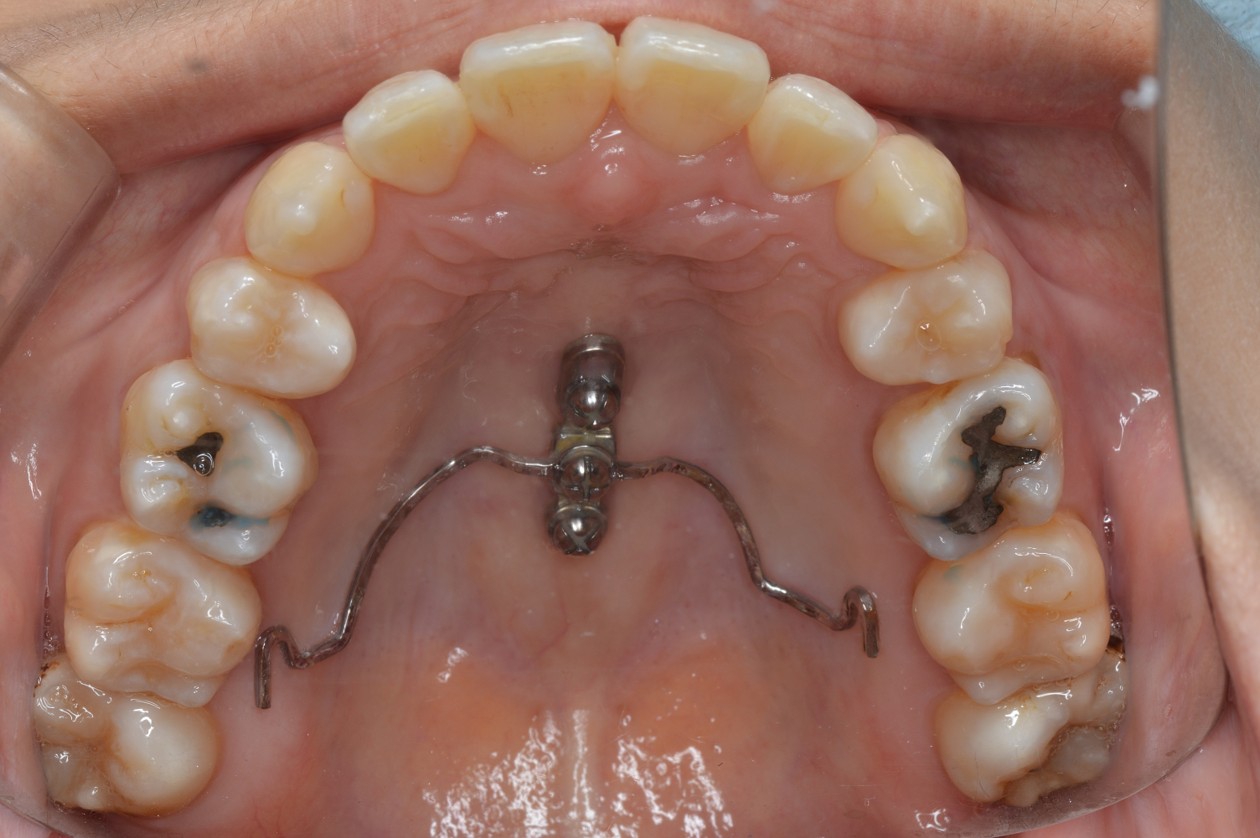

症例2

| 項目 | 詳細 |

|---|---|

| 患者様データ | 30代 女性 |

| 来院時の主訴 | 「右上の、内側に生えている歯が邪魔。」 |

| 矯正法 | 上の歯2本、下の歯2本、親知らず3本を抜歯しての矯正 |

| 通院期間 | 3年6ヶ月 |

| 治療費 | 総額:1,230,000円(税抜) 【内訳】 精密検査50,000円、メタルワイヤー矯正800,000円、月に1度の調整料5,000円、後戻り防止のリテーナー35,000円×2 |

| リスクと副作用 |

①歯を動かす事による痛みがあります。また、装置に慣れるまでは、口内炎ができやすいです。 ②歯肉が退縮するリスクがあります。装置が全ての歯に付くので、ハミガキが難しくなります。 ③長期的なメインテナンスが必要 |

| ここがこだわりのポイント!☝ | こちらの患者様は上の歯が1本内側に生えていましたが、奥歯の噛み合わせの方が問題でした。ハサミ状咬合といい、奥歯が極端に外側に向いており、下の歯と噛み合っていない状態でした。ハサミ状咬合は長期的にみると、前歯に大きな負担がかかったり、磨きにくい事による虫歯や歯周病になりやすいなどのリスクがあります。治療期間はかかりましたが、見た目の良さだけでなく、機能的にも改善しました。 |